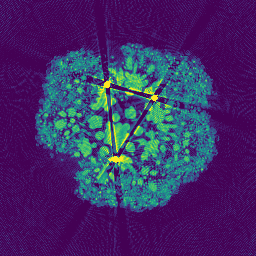

CBCT reconstruction with differentiable Gaussian primitives and our polychromatic X-ray model.

Our method jointly models projection and reconstruction by optimizing per-Gaussian material parameters together with the global X-ray response. A physics-based attenuation model decomposes material behavior into Compton and photoelectric components, enabling accurate polychromatic forward projection and effective metal artifact reduction without metal masks.